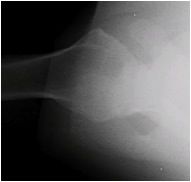

At the University of Washington Shoulder and Elbow Service we are seeing increasing numbers of patients referred with chondrolysis of the shoulder (glenohumeral joint). To date each of these cases has been associated with shoulder arthroscopy and the post-arthroscopic infusion of local anesthetics. The X-ray appearance and the surgical pathology consistently demonstrate the complete loss of articular cartilage not the focal loss that might be associated with mechanical damage from for example suture anchors. In none of these cases did infection or the use of intra-articular radiofrequency energy appear to be associated factors. Below are a series of radiographs and surgical photographs from these patients presented to demonstrate the characteristic features of this condition. Each of the patients was between 21 and 45 years of age and each had an arthroscopic procedure to address instability or a SLAP tear.

Axillary View